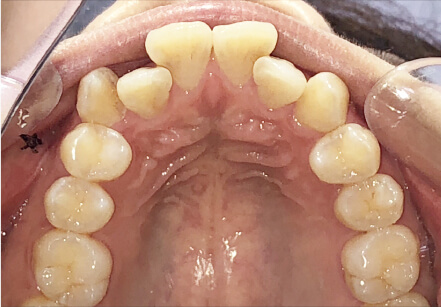

9歳

/

女性

相談内容

マイオスマイルからの移行

カウンセリング・診断結果

上11捻転、上33スペース不足、インビザで歯列矯正

治療内容・方法

全額アライナー矯正 クリアコレクト

術後の経過・現在の様子

リンガルアーチ使用

治療のリスク

痛み・歯根吸収・歯肉退縮・虫歯・後戻り

費用・治療期間

(マウスピース矯正のみ)440,000円+220,000円 月々27,500円、9ヶ月+myo1年10ヶ